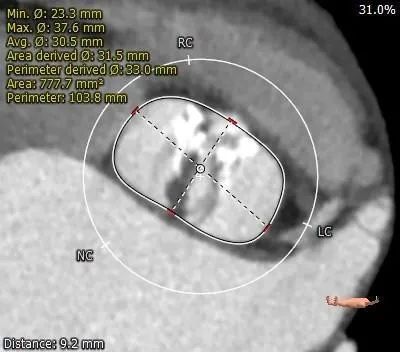

主动脉根部测量:

钙化分布: